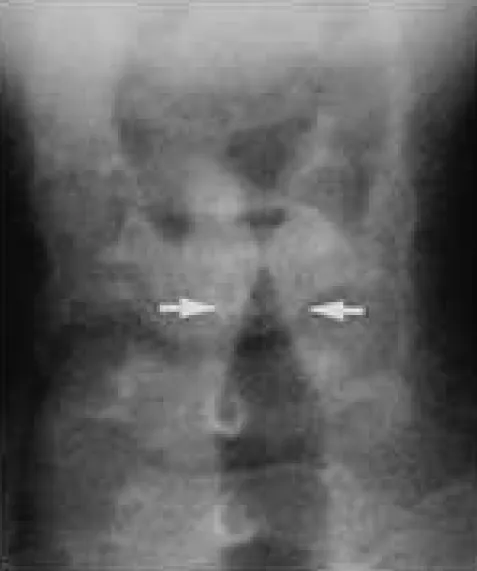

這題的解題核心在於辨識圖片中的典型X光影像特徵,並結合題幹描述的臨床症狀,判斷疾病診斷及相關的病原學知識。圖片中白色箭頭所指的氣管次聲門區(subglottic region)呈現典型的「尖塔徵象」,這是哮吼(Croup)的經典影像學表現。